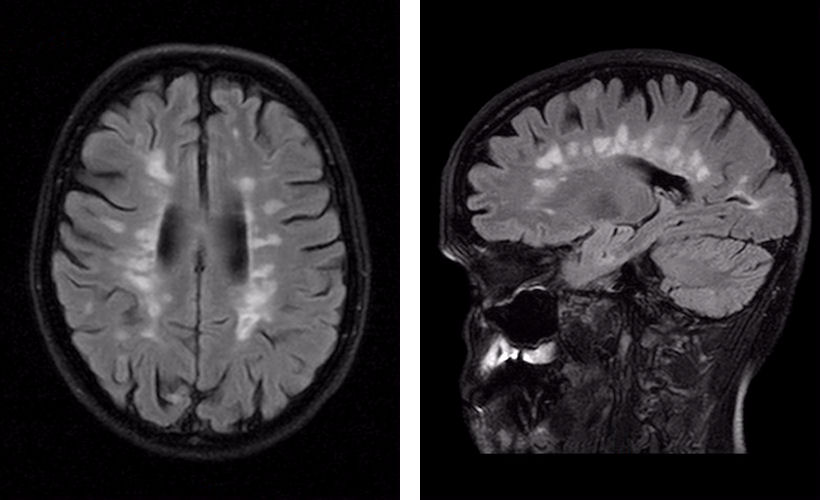

Демиелинизирующие заболевания мозга: МРТ изображения